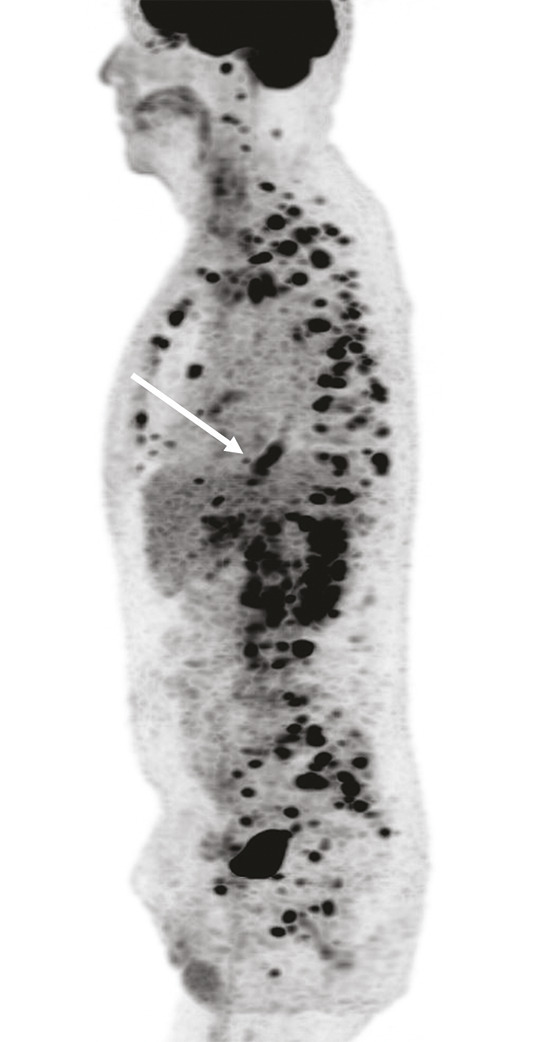

Ce patient de 63 ans était adressé pour bilan de douleurs abdomino-pelviennes associées à des adénomégalies cœliaques et lombo-aortiques dans un contexte d’altération de l’état général. La tomographie par émission de positons au fluorodésoxyglucose distinguait de multiples foyers hypermétaboliques ganglionnaires et osseux (fig. 1), ainsi qu’un hypermétabolisme intense du bas œsophage correspondant à un adénocarcinome. Il existait également un hypermétabolisme circonférentiel de la veine jugulaire interne gauche, s’étendant jusqu’au tronc veineux innominé, avec un aspect spontanément hyperdense au scanner (fig. 2). Ces anomalies étaient très évocatrices d’un thrombus. L’échographie veineuse en mode Doppler a confirmé ce diagnostic.